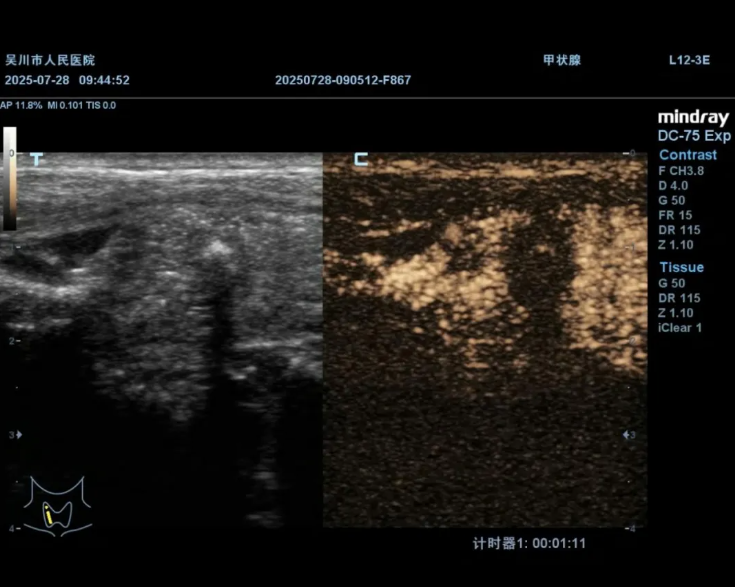

术前造影,明确结节内部情况与周围组织关系

术后超声造影

明确消融范围覆盖结节,确保消融效果